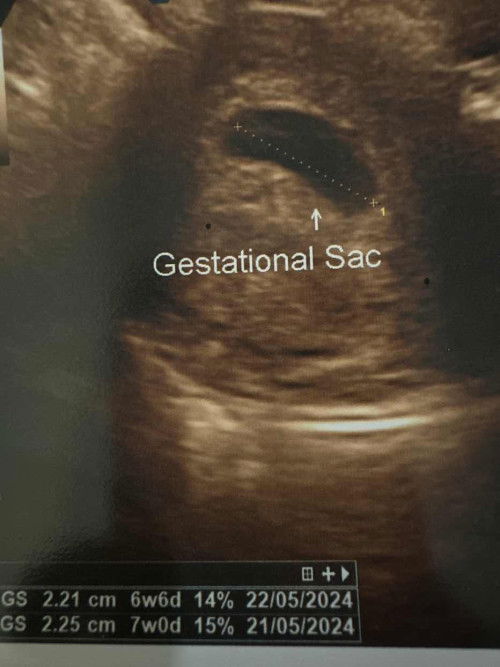

Belum nampak janin

Bun, normal gak kalo usia kehamilan sdh 7-8 minggu tp blm terlihat janin? Waktu usg baru keliatan kantung janin membesar dr 2minggu lalu dan bakal saluran makanan bayi. Mohon pencerahanny bun takut kenapa”, ini anak pertama 🥹